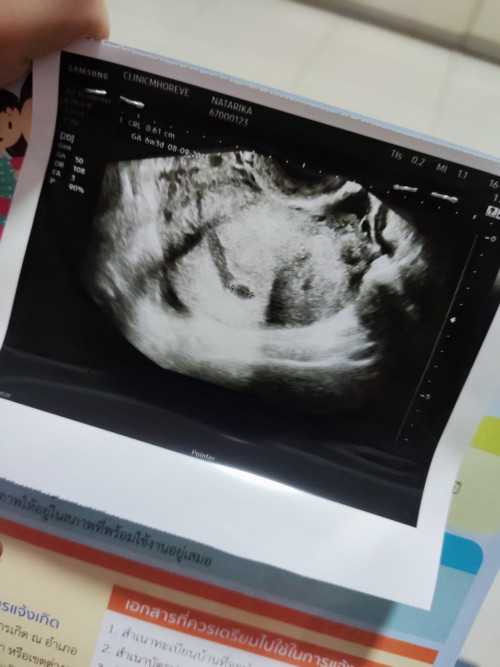

อัลตร้าซาวด์ตอน6วีค1วัน

สอบถามหน่อยค่ะ แม่ๆอัลตร้าซาวด์ดูลูกตอนกี่วีคค่ะ บ้านนี่6วีค1วันหมอบอกตัวน้องยังเล็กเกินไปเลยไม่เห็นหมอนัดอีกวันที่11มีแม่ๆคนไหนซาวด์ตอน6วีคแล้วไม่เจอตัวเด็กบ้างไหมค่ะ#ขอบคุณล่วงหน้านะคะ

บ้านนี้6w พอดีเจอตัวกับหัวใจน้องแล้วคะ

ซาวด์ week6 ไม่เจอเหมือนกันค่ะ มาเจอตอน week8

6วีค1วัน ไม่เจอเหมือนกันค่ะ แม่ลุ้นมาก

ไม่เจอเหมือนกันค่ะ จะเจอช่วง 7-8 วีคค่ะ

6วีค3วันยังไม่เจอตัวน้องเหมือนกันค่ะ

ซาวด์ดูตอน6วีคค่ะ​ เห็นน้องชัดเจนมาก